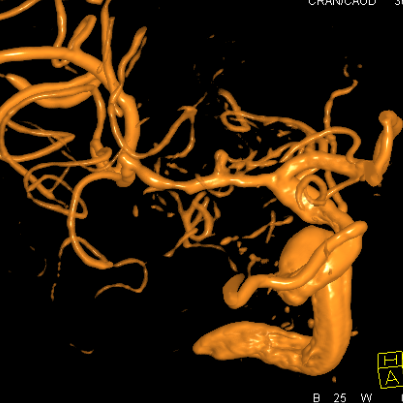

3、病变为长节段,M1上干已经闭塞;

4、病变累及一个粗大的豆纹动脉,这个动脉又发出众多分支豆纹动脉,一旦闭塞,后果严重,直接导致患者肢体瘫痪,手术风险极高;

5、粗大豆纹动脉的远端和近端都有一个狭长的血管变细

右侧MCA长节段血管变细狭长

长节段MCA血管狭长变细,尤以近端为重

重建的形态

血管形态